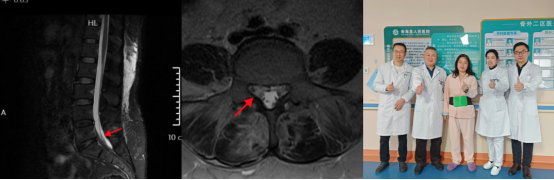

术前影像资料显示L5/S1巨大脱出椎间盘并向近端高度游离

术后复查MRI显示脱出椎间盘完全摘除,

神经松解彻底,患者术后恢复良好